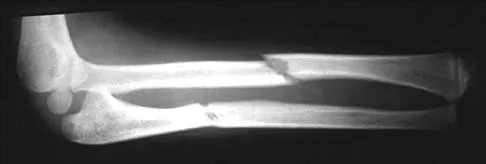

Figure 6 shows the radiograph of a 14-year-old baseball player who felt a pop and had an immediate onset of pain in his elbow after a hard throw from the outfield. The best course of action should be to